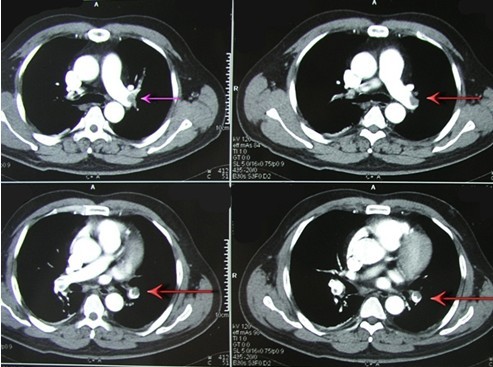

图4 下肢动脉超声示双下肢动脉粥样硬化闭塞征

图5 下肢静脉超声示左下肢深静脉血栓栓塞